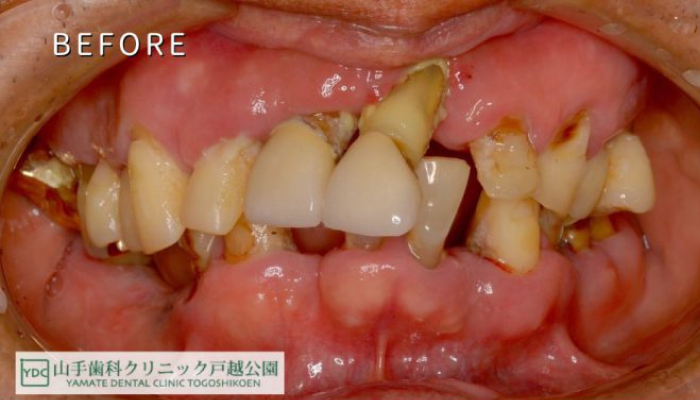

歯がボロボロになっている

長年の治療を繰り返した結果、噛み合わせが崩壊している。

多くの患者様が「なぜこんなに歯が悪くなるのか分からない」と悩みを抱えて当院を訪れます。歯周病インプラント治療を専門に行う私たちは患者様一人ひとりのお口全体を丁寧に診断し、トータルで健康な噛む力を取り戻す治療を提供致します。